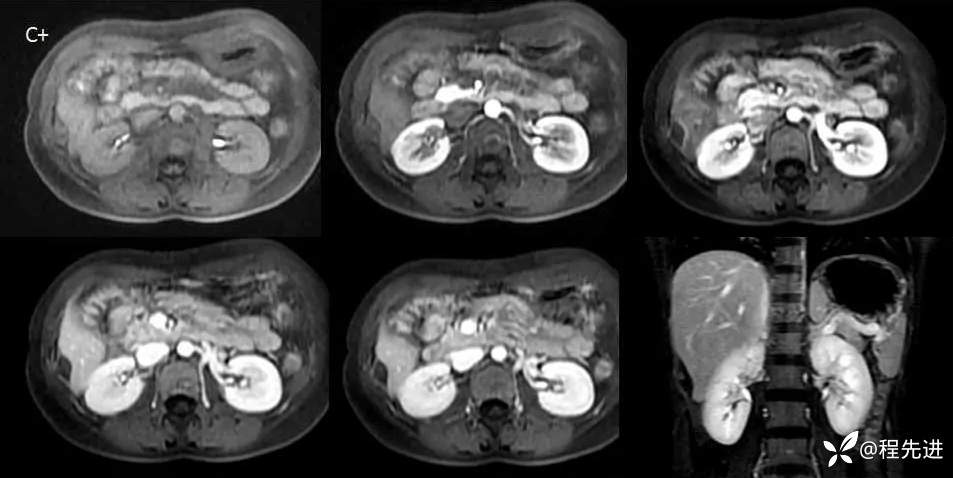

MRI检查: